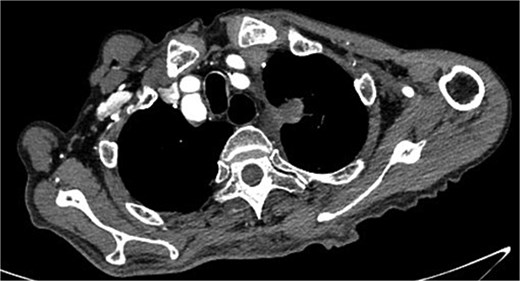

Despite recovery, the patient remained physically exhausted and required ongoing rehabilitation. In May 2023, after a COVID-19 infection, the patient experienced blood in phlegm. CTA confirmed successful aneurysm repair with no endoleak (Fig. 3). Thus the patient was hospitalized in the respiratory department. Relevant pulmonary examination indicators and lung CT results revealed no lung lesions associated with blood in sputum (Fig. 4). However, throughout July, 2023, intermittent blood in phlegm continued, and a CTA on July 19, 2023, revealed a type IV endoleak (Fig. 5). Conversely, aortography on July 27, 2023, showed no obvious endoleak. Closed drainage of the left thoracic cavity was performed, but blood in phlegm recurred on August 9, 2023. A Gore C-TAG stent graft was deployed in the thoracic aortic arch, with its proximal end anchored at the ostium of the left subclavian artery stent graft to ensure complete coverage of the endoleak site both proximally and distally(Fig. 6). Post-surgery, blood in phlegm symptoms abated.

In July 2023, endoleak was observed upon reexamination, possibly of stent graft origin.